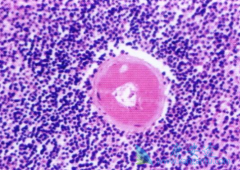

特发性巨球蛋白血症( WM) 是一种罕见的、缓慢生长且无法治愈的非霍奇金淋巴瘤,治疗方案有限。不过就是昨天,艾伯维宣布,美国FDA批准依鲁替尼(Ibrutinib)联合 美罗华 (RITUXAN)治疗成人特发性巨球蛋白血症。此次批准,意味着第一种也是唯一一种特 ...